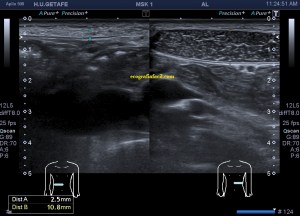

Exploración ultrasonográfica en la consulta de fisioterapia:

La ecografía muscular realizada evidencia una pérdida del patrón muscular normal en

el esternocleidomastoideo, con engrosamiento del mismo y semiología heterogénea en su tercio distal. Hay ganglios locorregionales hipoecogénicos con un patrón claramente reactivo aunque mantienen su tamaño subcentimétrico (Imagen 5).

A la altura de la bifurcación carotídea (imagen 6) el ECM adopta una apariencia más normal, su semiología es la típica del músculo. hipoecogénico y homogéneo, con ese patrón normal de «cielo estrellado» en eje corto como dice, mi querido amigo en sus clases, el Prof. Javier Álvarez, que tan amablemente me ha cedido estas imágenes para compartirlas en el Blog.

Parece existir señal Doppler periférica a la región anómala, que se extiende desde tercio medio del ECM, en su vertiente posterior hasta por lo menos la articulación esternoclavicular, aunque podría extenderse a la región infraclavicular.